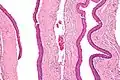

Odontogenic keratocysts have a diagnostic histological appearance. Under the microscope, OKCs vaguely resemble keratinized squamous epithelium;[14] however, they lack rete ridges and often have an artifactual separation from their basement membrane.[2]

The fibrous wall of the cyst is usually thin and uninflamed. The epithelial lining is thin with even thickness and parakeratinised with columnar cells in the basal layer which have focal reverse polarisation (nuclei are on the opposite pole of the cell).[12] The basal cells are an indication of the odontogenic origin as they resemble pre-ameloblasts. The epithelium can separate from the wall, resulting in islands of epithelium. These can go on to form 'satellite' or 'daughter' cysts, leading to an overall multilocular cyst.[9] Presence of daughter cysts is particularly seen in those with NBCCS.[12] Inflamed cysts show hyperplastic epithelium which is no longer characteristic of OKCs and can have resemblance to radicular cysts instead. Due to areas of focal inflammation, a larger biopsy is required for correct diagnosis of odontogenic keratocysts.[9]

Intermediate magnification of an odontogenic keratocyst showing a folded cyst.